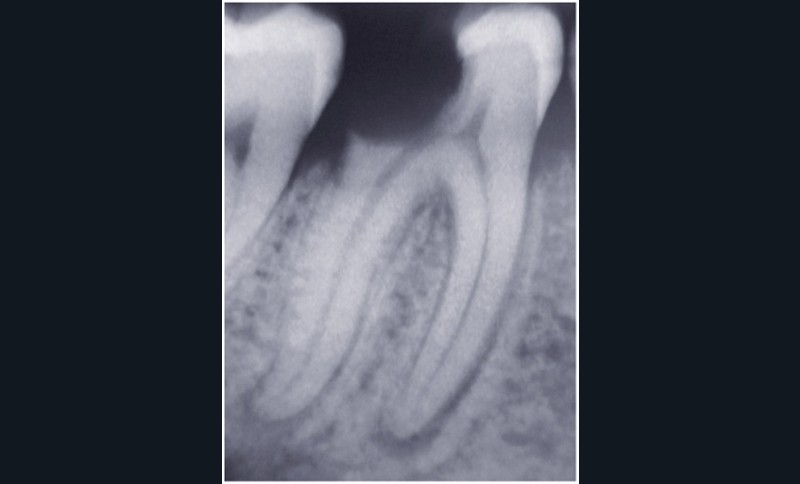

Dans un environnement parodontal sain, la chronologie des traitements conservateurs suite à la pathologie carieuse serait la suivante : le traitement endodontique de première intention, le retraitement endodontique et la chirurgie endodontique, voire l’amputation radiculaire. En cas d’échec, l’alternative implantaire pourra être envisagée (fig. 1).